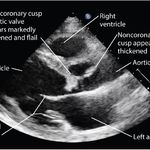

Echocardiogram Findings in Severe Infective Endocarditis of Aortic Valve